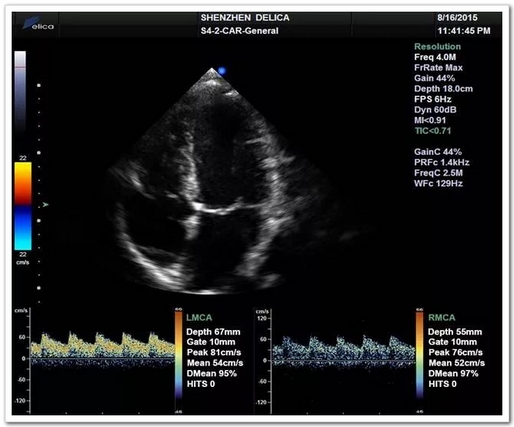

心脏超声与颅内血流同屏同步显示

全球唯一!